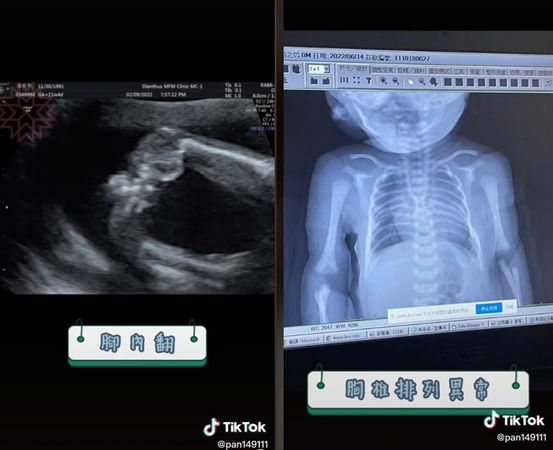

潘潘透過TikTok影片和大家分享她檢查出「異常寶寶」的懷孕心酸經歷,她在懷孕5個月時例行產檢於高層次檢查被檢查出胎兒有特殊疾病,醫生告訴他孩子有胸椎排列異常、腳內翻,甚至直言「嚴重的話,頸部以下都無法行動!」希望她與老公慎重考慮,是否要生下這個孩子,潘潘心痛坦言:「那一刻我覺得我的世界都瓦解了!」

潘潘說明,胸椎異常的機率是千萬分之一、腳內翻的機率則是千分之一,她無奈直言:「我這輩子買樂透連400塊都沒中過,這種比走在路上被雷劈到機率還要小的事情,我卻中了。」然而儘管如此,作為媽媽的她不肯放棄,打起精神瘋狂查詢各種資訊,安排羊膜穿刺檢查,找其他婦產科醫生、其他醫院做更詳細檢查、歷經各種轉診,甚至做了核磁共振,做更詳細一步的檢查,說什麼就是不肯輕易放棄寶寶:「我每天都裝沒事唱歌給我的寶寶聽、為他加油打氣,我不敢跟身邊的人提,很努力在過每一天....」